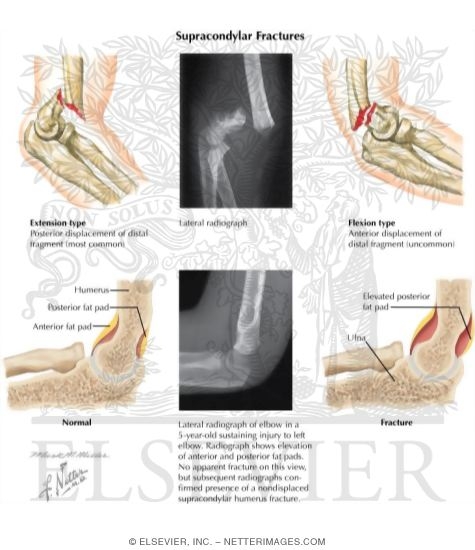

Supracondylar Fracture

Labeled - Thompson Ortho Anatomy 2E